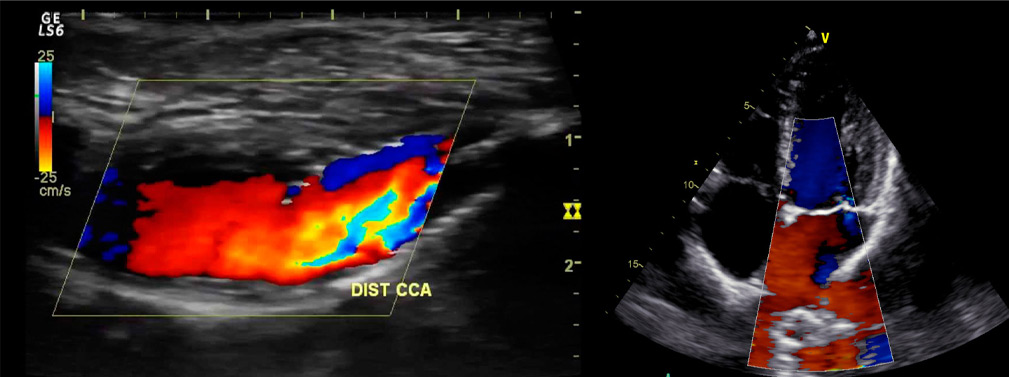

Ecodoppler

Es un tipo de ultrasonido que utiliza ondas sonoras para evaluar cómo circula la sangre a través de los vasos sanguíneos. Es una prueba no invasiva que también permite visualizar el flujo sanguíneo en los tejidos.

La ecografía Doppler puede ayudar a diagnosticar una multitud de afecciones, como coágulos sanguíneos, arterias obstruidas o estrechas y aneurismas.

Se realizan ecodoppler de las siguientes regiones:

Ecodoppler abdominal

Ecodoppler testicular

Ecodoppler de tiroides

Ecodoppler mamario

Ecodoppler ginecológico.

Ecodoppler de partes blandas

Ecodoopler articular

Ecodoppler obstétrico

Un ecodoppler fetal es un tipo de ecografía que evalúa el flujo sanguíneo en las arterias y venas de la madre y del bebé. Esta ecografía permite detectar alteraciones en la llegada de sangre desde la placenta hacia el bebé. Está indicada en algunas enfermedades maternas como hipertensión arterial, diabetes, trombofilias y en casos de restricción de crecimiento del bebé.